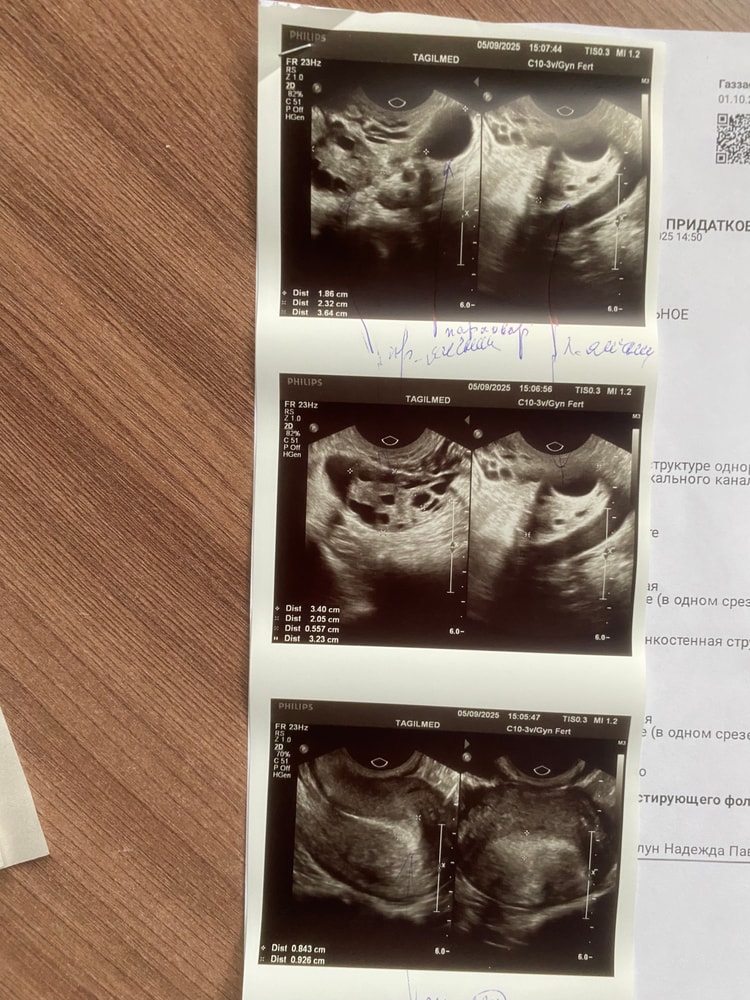

Месячный циклДевочки добрый день , я уже не знаю куда и с чем обращаться , подскажите . Планируем ребенка уже 2 года , врачи говорят овуляция то есть то нет , цикл не регулярный постоянные задержки , врач выписал 3 месяца ОК, 3 мес утрожестан свечи и как бы дальше должно быть все в норме . НО НЕТ. После того как проставила последний мес свечи , начались месячные и шли всего 1-2 дня , при обычных 5-6 . В этом месяце снова задержка . Была на узи , говорят овуляции не было и ближайшие 2 недели месячных не видят . что делать , может кто то сталкивался , что вам помогло? Само настроилось или препараты какие то пили . Назначили операцию ГСГ проверка маточных труб , а я не могу записаться на нее так как цикл не регулярный а запись за месяц почти . Я уже руки опускаю , не знаю что делать . Отвлечься вообще никак не получается , кто поймет тот поймет , это ожидание каждый мес убивает , сидишь как дура эти полоски высматриваешь , а оно вот так вот . Мне даже диагноз врач поставить не может . Плохо работают яичники , надо дать им отдохнуть , дали , а ничего не поменялось . Фото узи прикреплю может кто то разбирается , помогите , все ли так плохо как я думаю . Вроде узист сказала что ничего страшного не видит , но врачу бы показать .